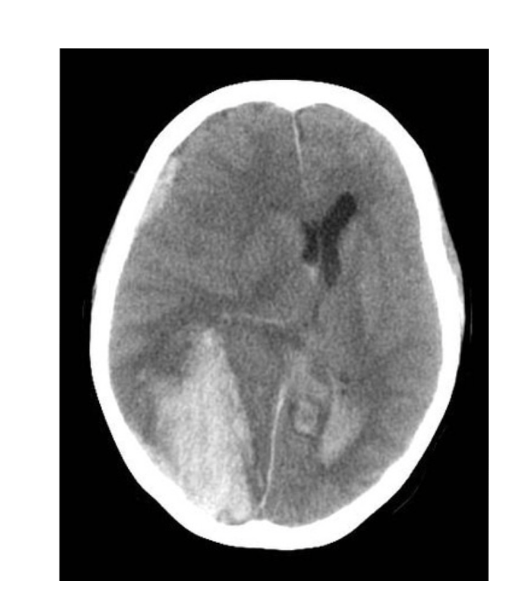

CT protocol + pathology?

• Brain C-

• Path = intraventricular haemorrhage

• Abnormal hyper attenuation in lateral ventricles indicating the presence of blood.